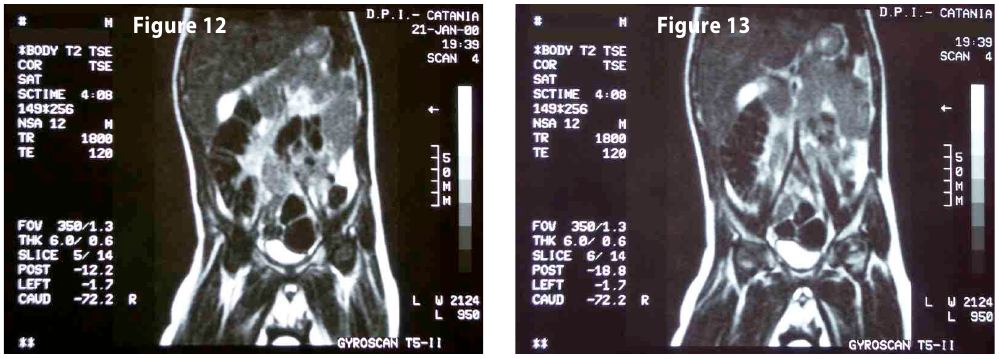

Complete objective response of neuroblastoma to biological treatment.

Figure10-11-12-...